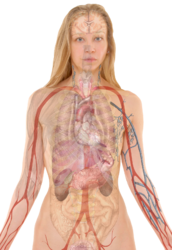

File:Tuberculosis symptoms.svg

| DescriptionTuberculosis symptoms.svg |

English: Main symptoms of different variants and stages of tuberculosis (See Wikipedia:Tuberculosis), with many symptoms overlapping with other variants, while others are more (but not entirely) specific for certain variants. Multiple variants may be present simultaneously.